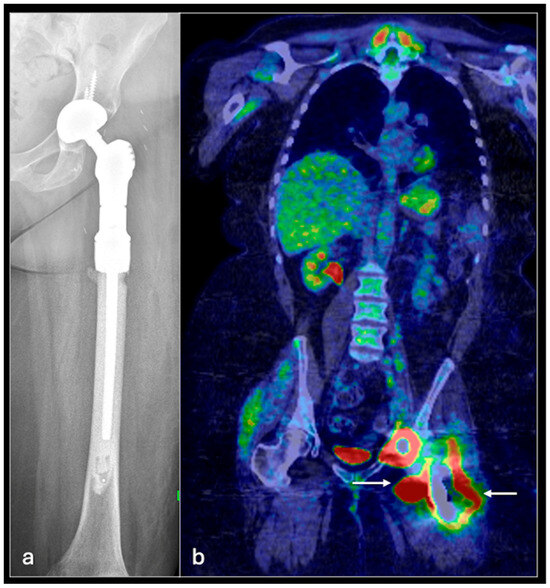

4.1. Osteosarcoma

- Plaza de Las Heras, I.; García Cañamaque, L.; Quílez Caballero, E.; Camacho-Arias, M.; Cárdenas Soriano, M.D.P.; Martel Villagrán, J. Positron emission tomography-magnetic resonance imaging applications in pediatric musculoskeletal tumors. Quant. Imaging Med. Surg. 2024, 14, 7825–7838. [Google Scholar] [CrossRef] [PubMed] [PubMed Central]